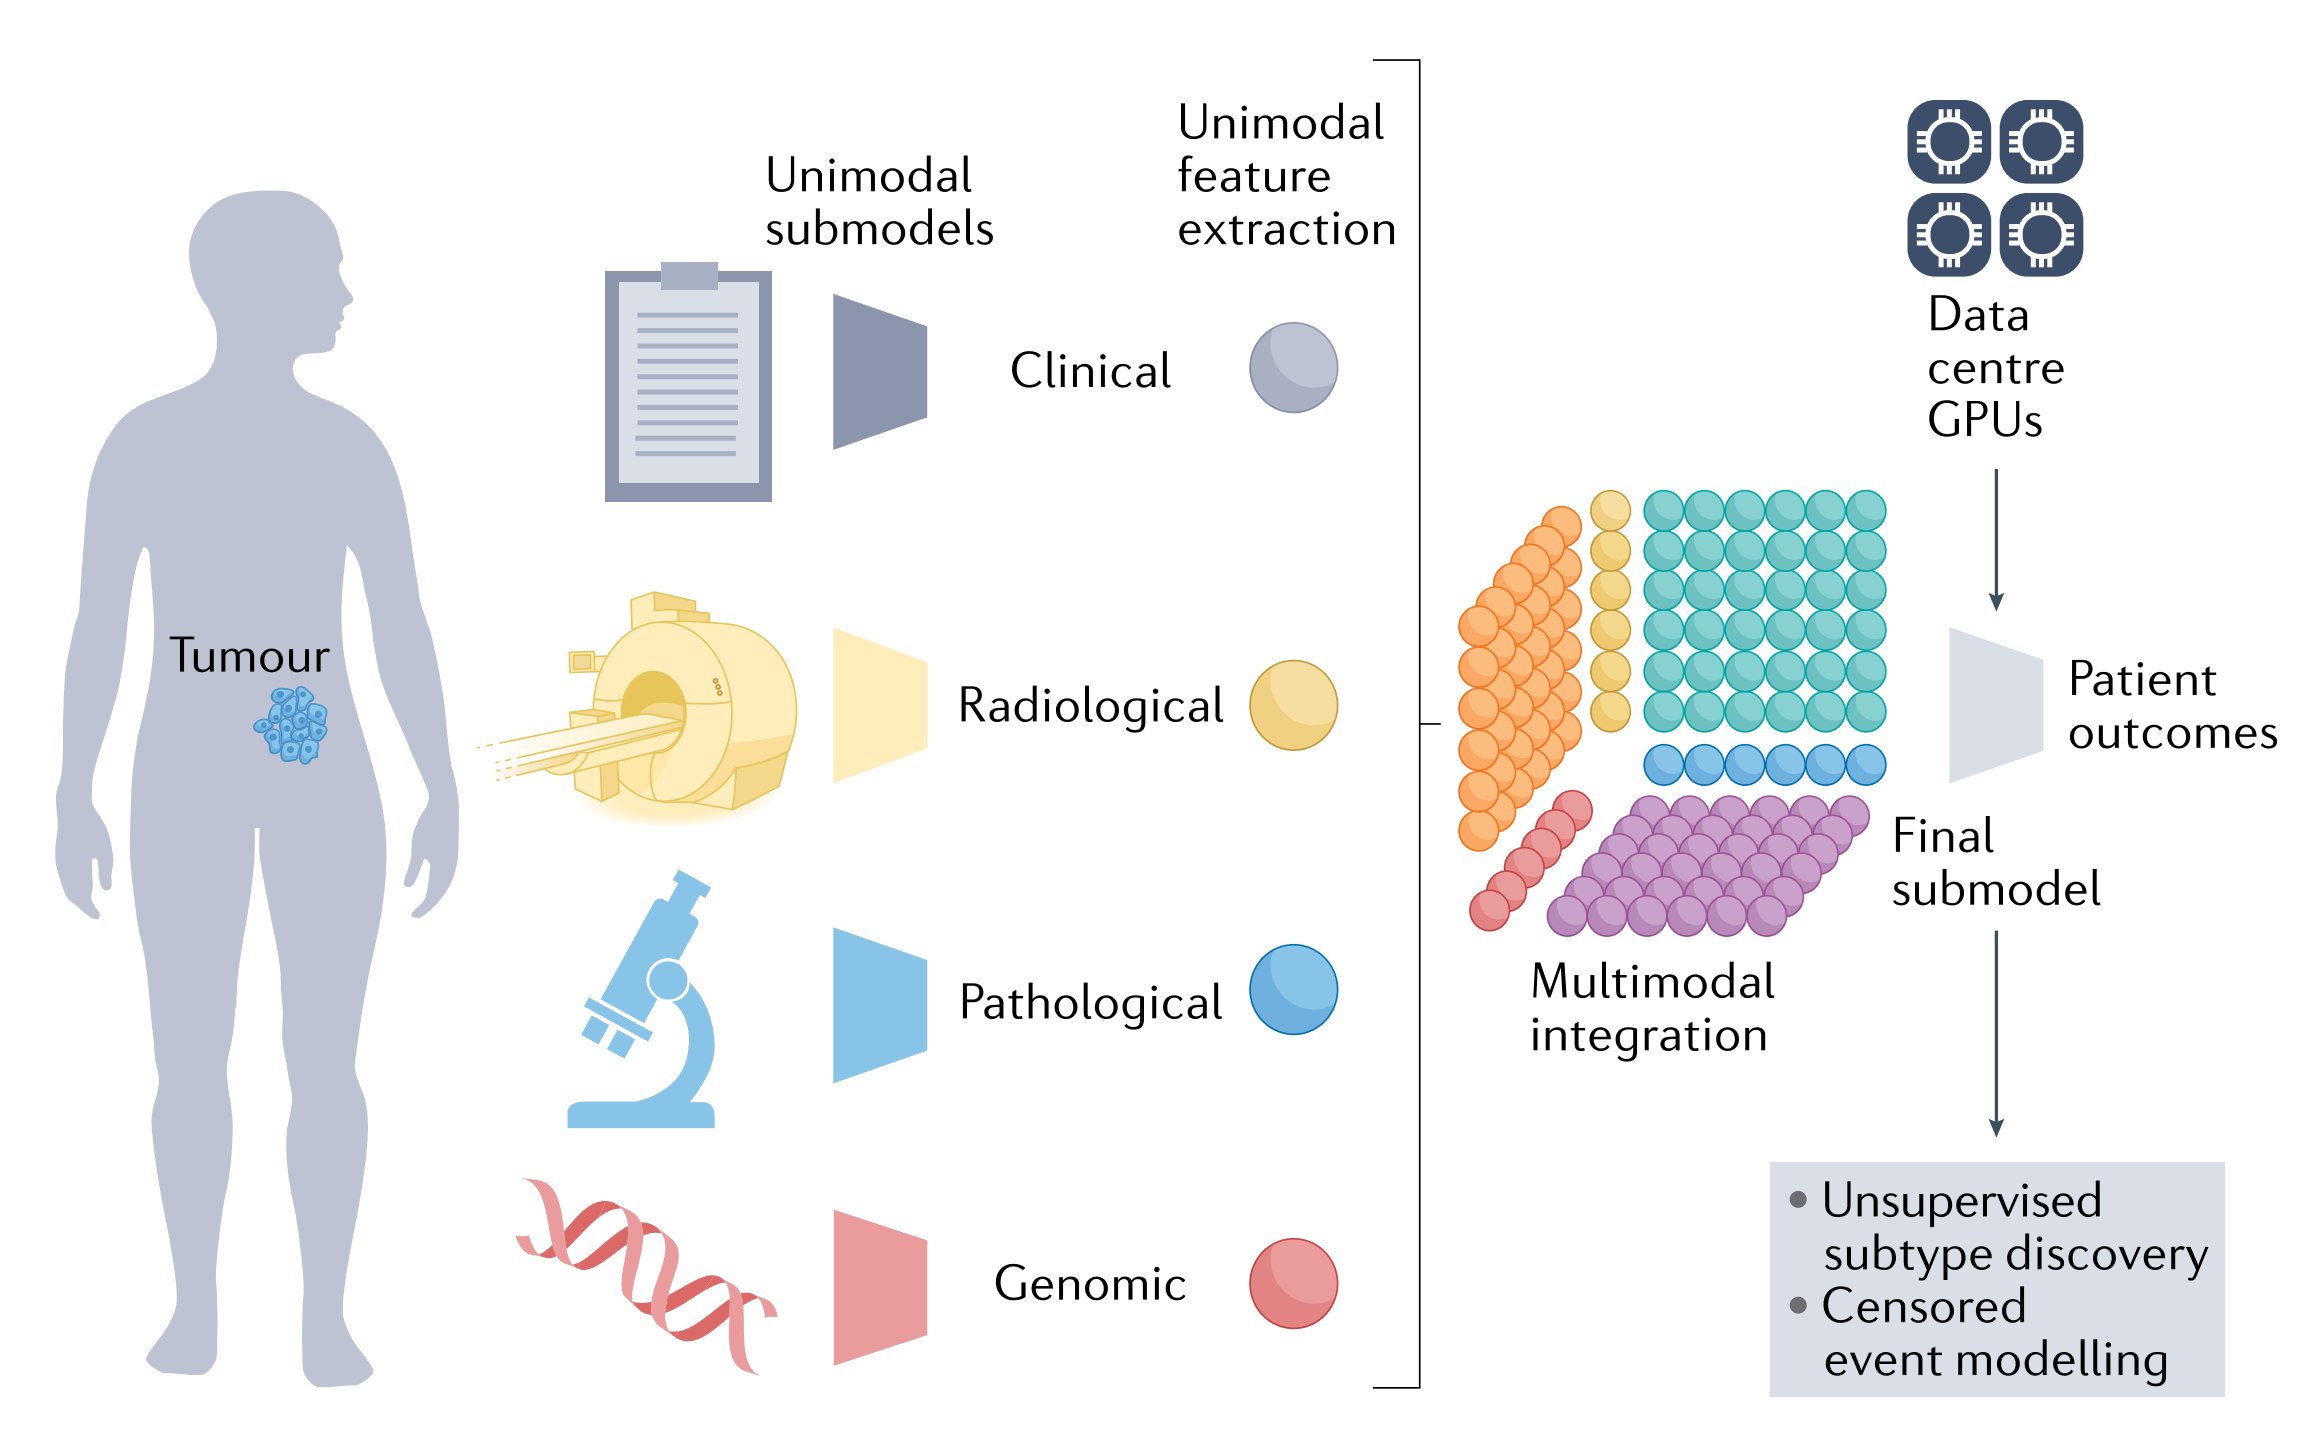

在上一节讨论的放射学、组织病理学、分子和临床领域中的这些单模态模型将成为综合多模态模型的构建块(图2)。

图 2 描述了多模态模型是如何整合不同数据模态的特征来推断患者结果的。在精准肿瘤学中,多模态模型能够同时考虑来自放射学、组织病理学、基因组学和临床信息等不同来源的数据,以提高对疾病状态和治疗结果的预测准确性。

以下是对图 2 中多模态模型整合过程的解释:

- 单模态特征提取:

- 在多模态模型中,首先从每个数据模态中提取特征。例如,从放射学图像中提取放射组学特征,从组织病理学图像中提取细胞和组织结构特征,从基因组数据中提取突变和拷贝数变异信息。

- 单模态子模型:

- 每个模态的数据特征被输入到对应的单模态子模型中。这些子模型是专门为处理特定类型的数据而设计的,能够捕捉该模态的特定信息。

- 无监督亚型发现:

- 对于某些模态,可能使用无监督学习方法来发现数据中的潜在结构或患者亚型,这些亚型可能与临床结果相关。

- 多模态整合步骤:

- 单模态子模型处理后,会有一个多模态整合步骤,该步骤生成跨模态的特征,即特征融合。这些融合特征旨在捕捉不同数据源之间的相互作用和关联。

- 最终子模型:

- 在多模态整合步骤之后,最终子模型会使用这些融合特征来推断患者的治疗结果,如生存时间、疾病进展或治疗响应。

- 数据中心 GPU:

- 多模态模型的训练和推断通常需要大量的计算资源,如高性能的图形处理单元(GPU)。

- 患者结果:

- 最终,多模态模型的输出是关于患者结果的预测,这些结果可以指导临床决策,如个性化治疗计划。

图 2 强调了多模态数据整合在精准医学中的潜力,通过结合不同数据源的信息,可以更全面地理解疾病的复杂性,并为患者提供更精确的诊断和治疗建议。